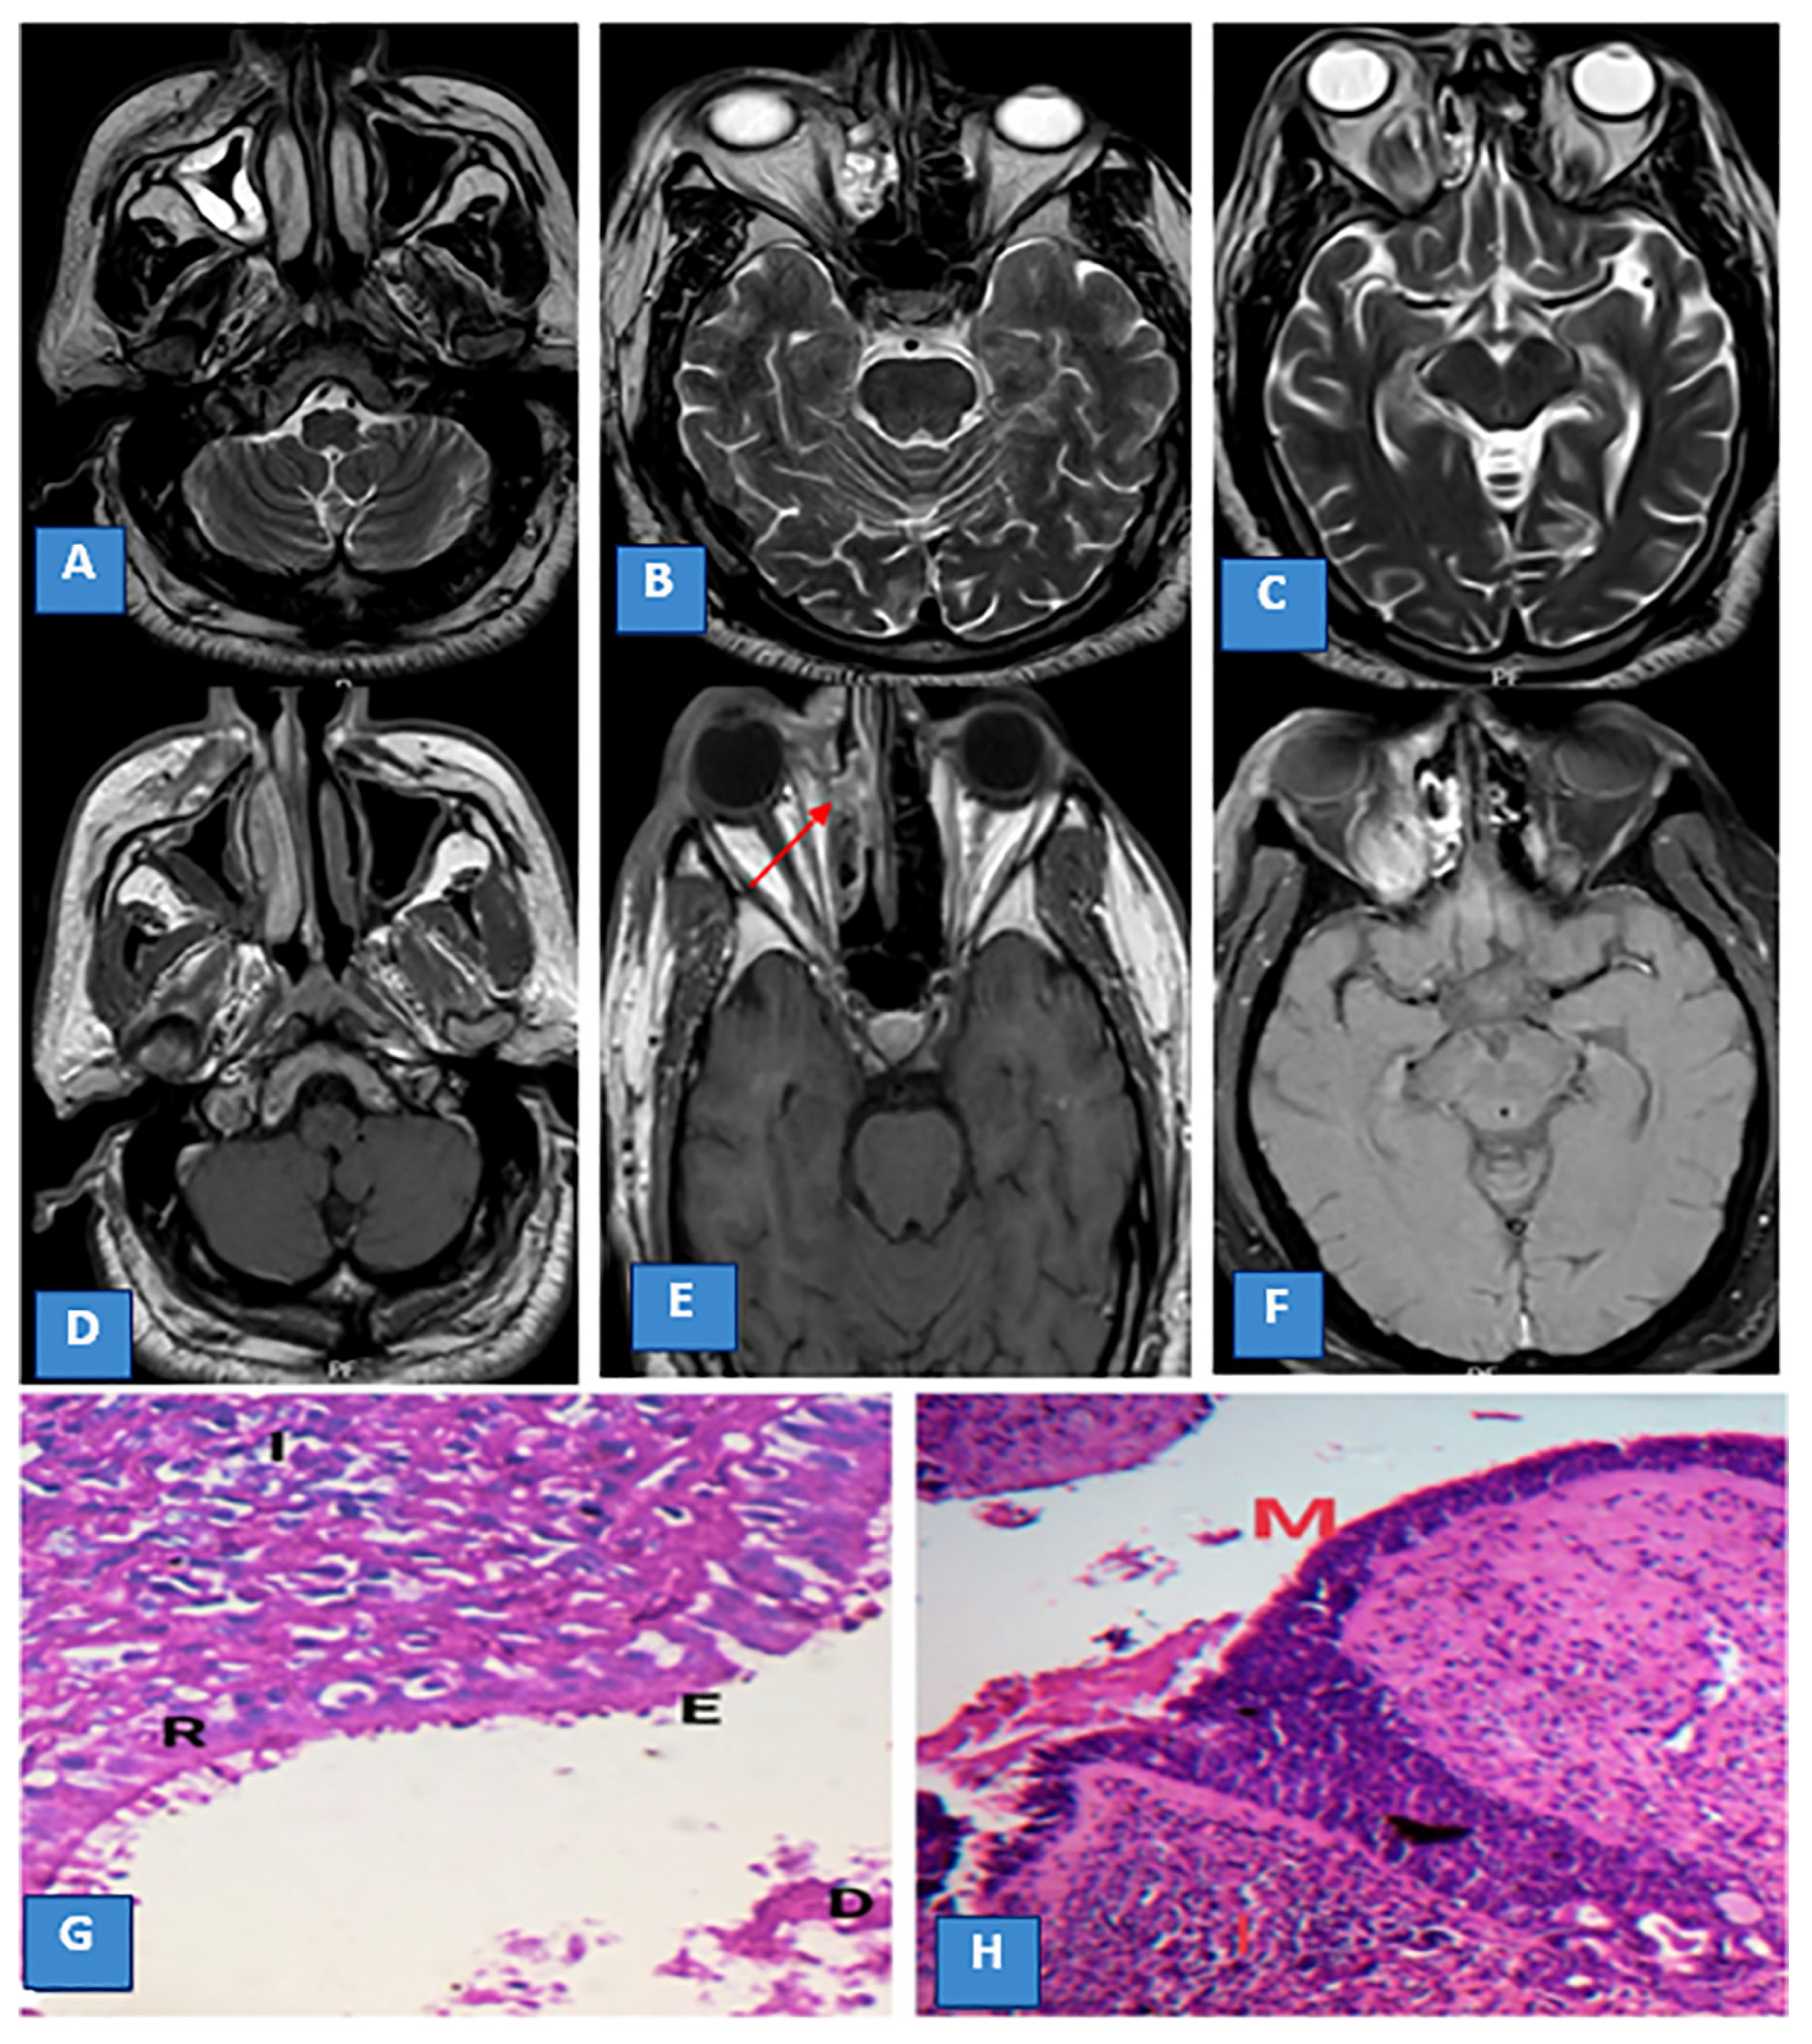

Magnetic Resonance Imaging Features of Rhino-Orbito-Cerebral Mucormycosis in Post-COVID-19 Patients: Radio-Pathological Correlation

3.3. MRI Findings and Signal Characteristics

3.4. Extrasinus Extension

3.5. Histopathological Findings